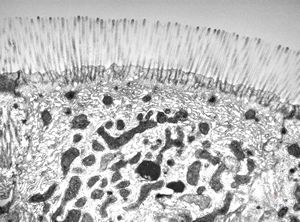

normal mucosa - jejunum - microvilli(anchored core rootlets)

normal mucosa - jejunum - microvilli